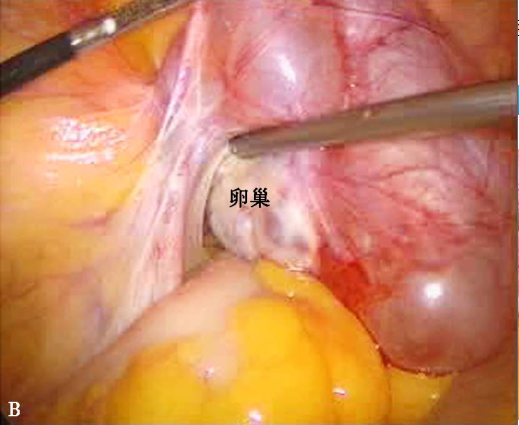

A.肠管、大网膜与子宫后方、右附件广泛粘连形成包块;B.右附件区包块来自右侧卵巢和输卵管,与周围组织粘连。

卵巢很少单独发炎,白膜是良好的防御屏障,卵巢常与发炎的输卵管伞端粘连而发生卵巢周围炎,称为输卵管卵巢炎,习称附件炎。炎症可通过卵巢排卵的破孔侵入卵巢实质形成卵巢脓肿,脓肿壁与输卵管积脓粘连并穿通,形成输卵管卵巢脓肿。输卵管卵巢脓肿可为一侧或两侧,约半数是在可识别的急性盆腔炎性疾病初次发病后形成,另一部分是屡次急性发作或重复感染而形成。输卵管卵巢脓肿多位于子宫后方或子宫、阔韧带后叶及肠管间粘连处,可破入直肠或阴道,若破入腹腔则引起弥漫性腹膜炎。